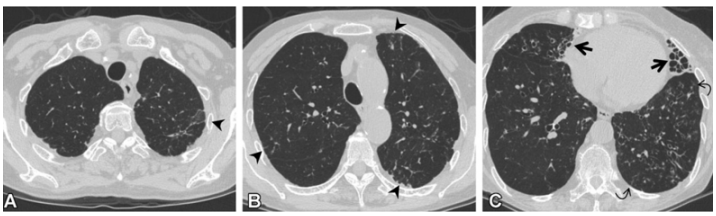

(1)感染性疾病:病毒性?细菌性?真菌?非典型病原体?吸入性肺炎?(2)非感染性疾病:心衰?急性肺栓塞?自身免疫性疾病?麻醉/手术相关肺损伤?急性间质性肺炎?回顾分析患者入院时胸部CT: 双肺靠近外周近胸膜处有轻微细小间质样改变(图4)。诊断:急性间质性肺炎;Ⅰ型呼吸衰竭;左肺下叶部分切除术后;高血压病。ECMO支持;呼吸机支持;甲泼尼松80 mg q12h,尼达尼布;镇静镇痛;抗感染;营养支持。ECMO第6天, 术后第18天, 肺部病变进一步加重(图5)。血气分析: pH 7.543, PaO2 154 mmHg, PaCO2 33.2 mmHg(ECMO, FiO2 100%, MV FiO2 60%)。术后第26天复查胸部CT未见改善。患者最终死亡。笔者团队也曾接诊过一例早期肺癌患者,2013年和2014年随访肺部结节均无明显变化。2015年胸部手术后2天,两肺变白(图6)。当时医生警惕性非常高,立刻行胸部CT检查并予相应治疗,患者最终存活。2022年RadioGraphics 杂志报道一例85岁女性腺癌患者奥希替尼治疗5个月后。图7-A和B为治疗前胸部CT图像,可见右肺中叶有肿块(A中箭头)。胸膜下区域磨玻璃改变和网状结构(箭头)提示存在间质性肺异常(Interstitial Lung Abnormalities,ILA)。治疗5个月后的轴位CT图像显示肿块(C中白色箭头)、弥漫性磨玻璃改变和合并症(黑色箭头)。图源:Radiographics, 2022, 42(7):1925-1939.另一例66岁右上肺鳞癌患者,术前CT显示肿块(图8-A中箭头)位于肺右上叶。轻度磨玻璃改变(箭头),提示ILA,见于胸膜下区域。图8-C和D为术后CT,显示弥漫性磨玻璃样改变和实变(箭头),牵引性支气管扩张症(图8-C中箭头),也可见胸腔积液(图8-D中箭头)。图源:Radiographics, 2022, 42(7):1925-1939.